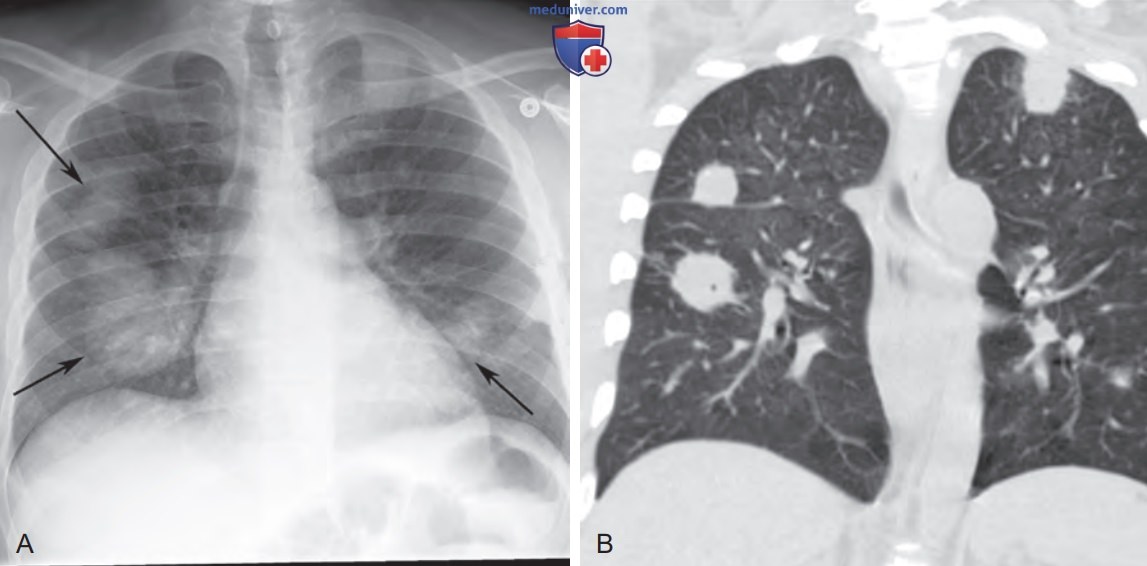

Инфекции легких при ВИЧ, СПИД на рентгенограмме и компьютерной томограмме (КТ)

Нокардиальная и криптококковая инфекция у пациента, перенесшего трансплантацию почки. (А) На рентгенограмме органов грудной клетки в задне-передней проекции показаны множественные двусторонние узелковые и объемные образования легких (стрелки). (B) На фронтальной бесконтрастной томограмме видны двусторонние узелковые образования легких. Круг дифференциальной диагностики при узелковых и объемных образованиях легких у пациента, перенесшего трансплантацию солидного органа, включает инфекции (например, грибки и Nocardia), посттрансплантационное лимфопролиферативное заболевание и метастазы